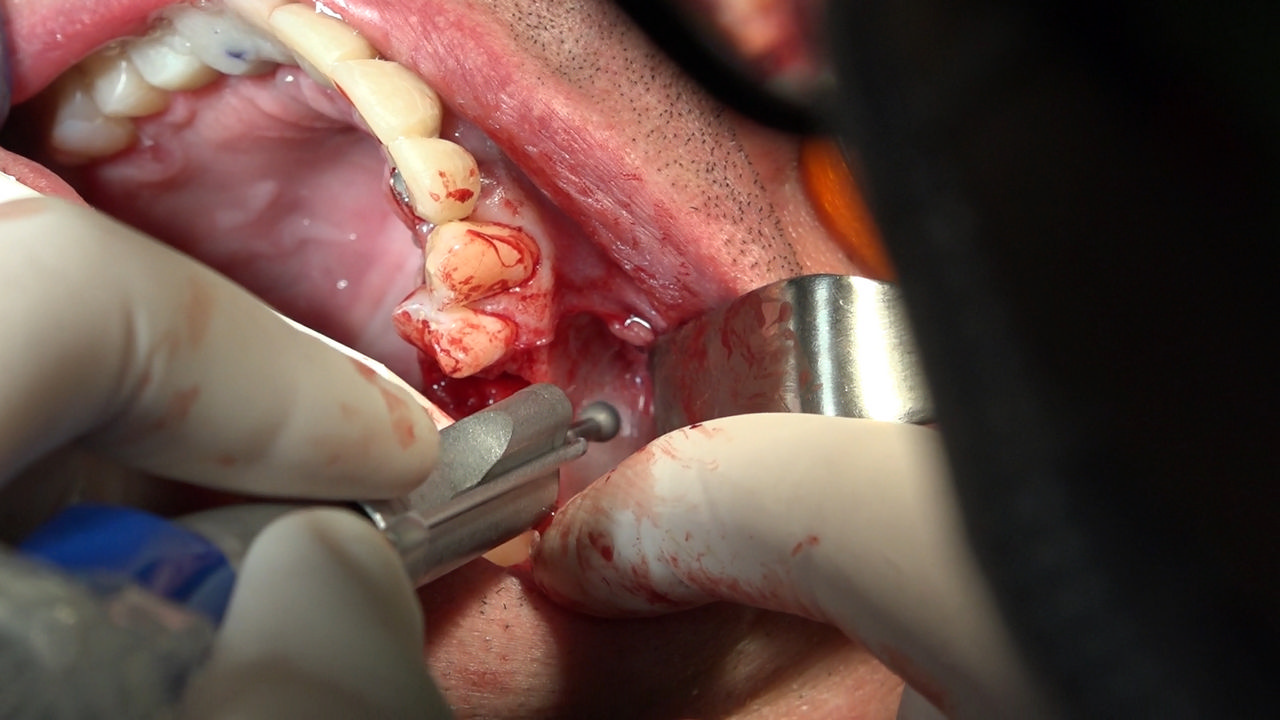

7 Sesja X Sezonu Practiculum Implantologii, w której brali udział kursanci z Grupy A i B, obejmowała implantacje wykonane systemem Axiom, procedury regeneracyjne tkanki kostnej i zabieg sinus lift oraz procedury implantoptotetyczne. Ten zakres szkolenia poprowadziła dr Małgorzata Piotrowska. Protetyka na implantach, to finalny etap leczenia implantologicznego decydujący o uzyskaniu harmonijnego łuku zębowego, okluzji oraz szczelności połączeń, a więc zadowoleniu Pacjenta i powodzeniu całego procesu leczenia.

Jego sednem jest wybór optymalnego rozwiązania rekonstrukcji protetycznej uwzględniający bardzo wiele czynników o charakterze mechanicznym, funkcjonalnym i estetycznym, związanych ze stanem tkanki kostnej, jamy ustnej i uzębienia. Odbywa się już na etapie tomografii komputerowej i jest ściśle powiązany z częścią chirurgiczną, ponieważ prawidłowe zaplanowanie pracy i usytuowania implantów wspomagane plastyką tkanek miękkich, to dla procedur protetycznych baza wyjściowa. Zasady te są jak najbardziej oczywiste, zarówno przy samodzielnym wykonywaniu leczenia implantologicznego, jak i przy podziale zadań dla chirurga i protetyka, czyli pracy w duecie.